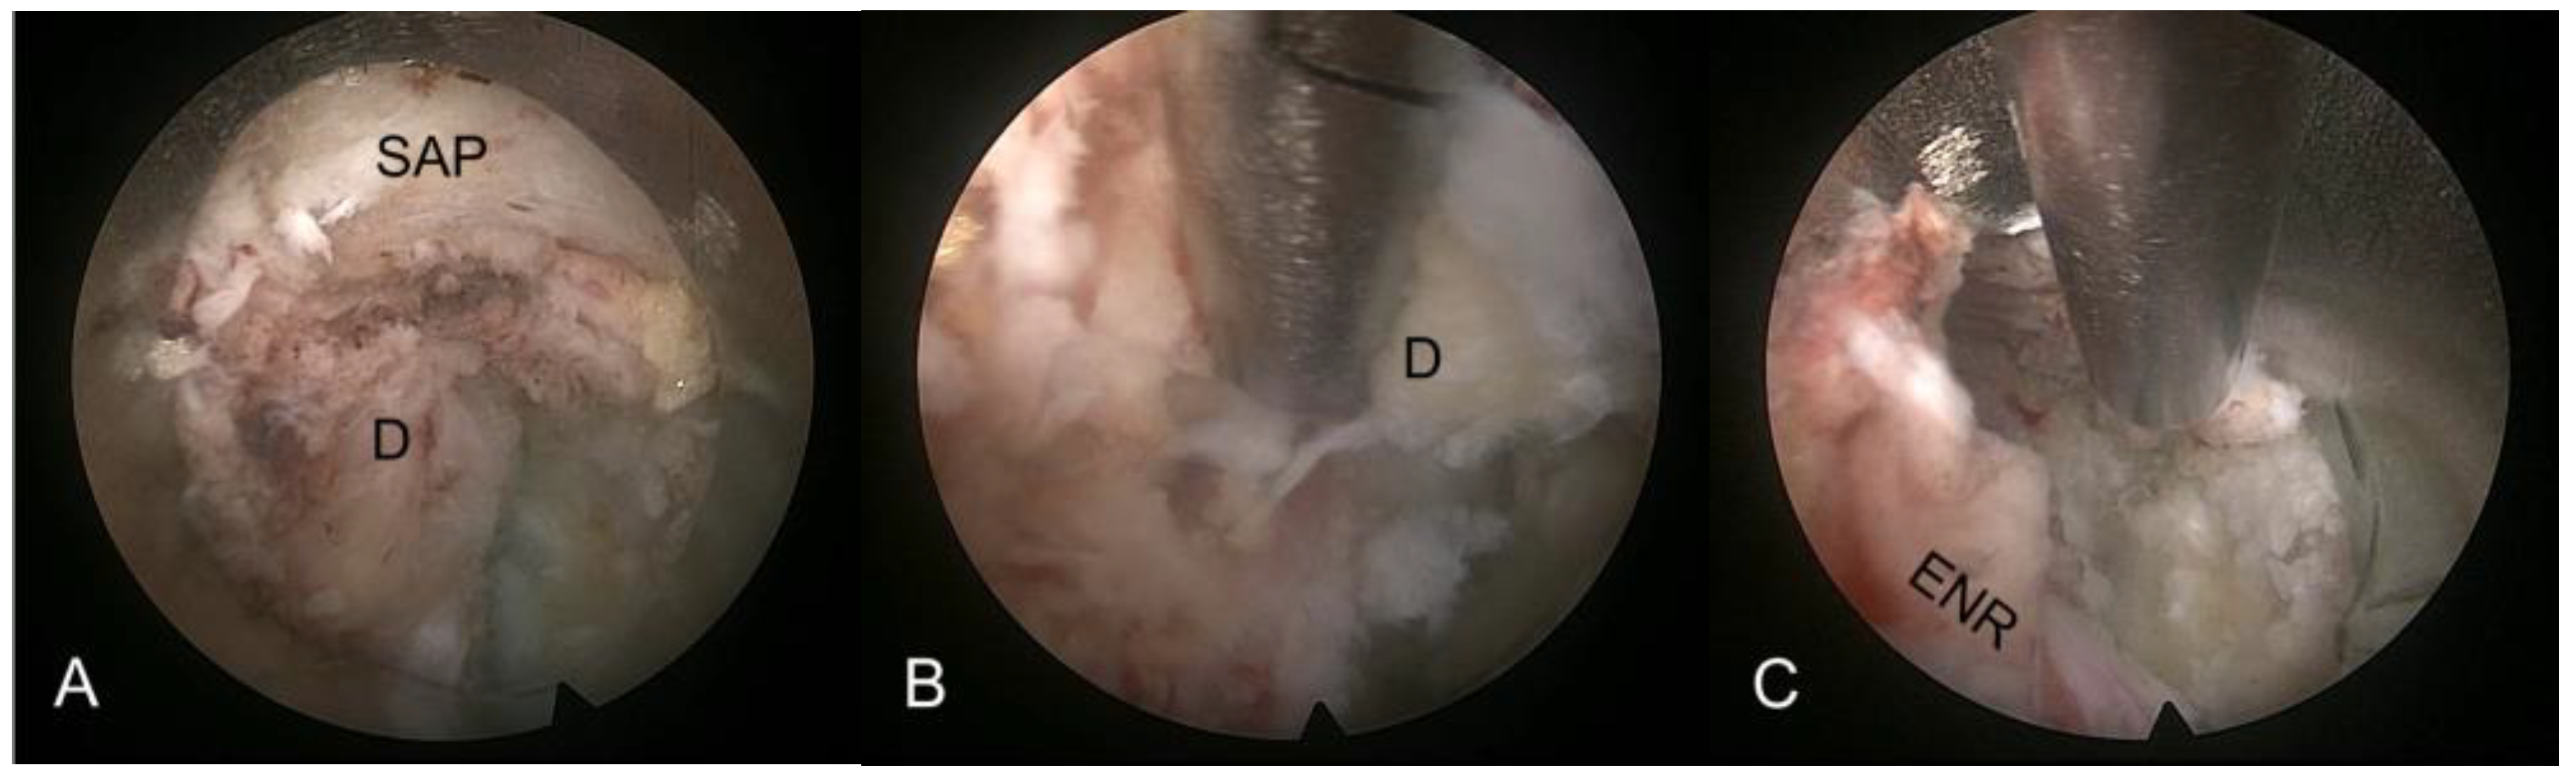

2.2.3. Selective Discectomy Under Endoscopic Visualization